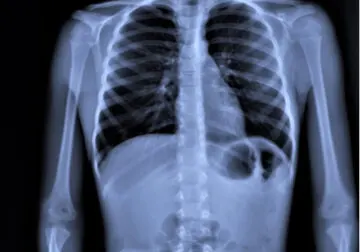

La neumonía es una infección que afecta a los alvéolos del pulmón. Estos son pequeños sacos cubiertos de vasos sanguíneos en los que se realiza el intercambio gaseoso, es decir, se expulsa dióxido de carbono (CO2) y se capta oxígeno del exterior. Por eso, son tan importantes las consecuencias de la neumonía en el cuerpo.

- Sustancias que atraen otras células de defensa, como los neutrófilos. A su vez, los neutrófilos producen secreciones purulentas. Estas pueden tapar los alvéolos impidiendo que se produzca el intercambio gaseoso y provocando sensación de ahogo porque no llega oxígeno a la sangre.